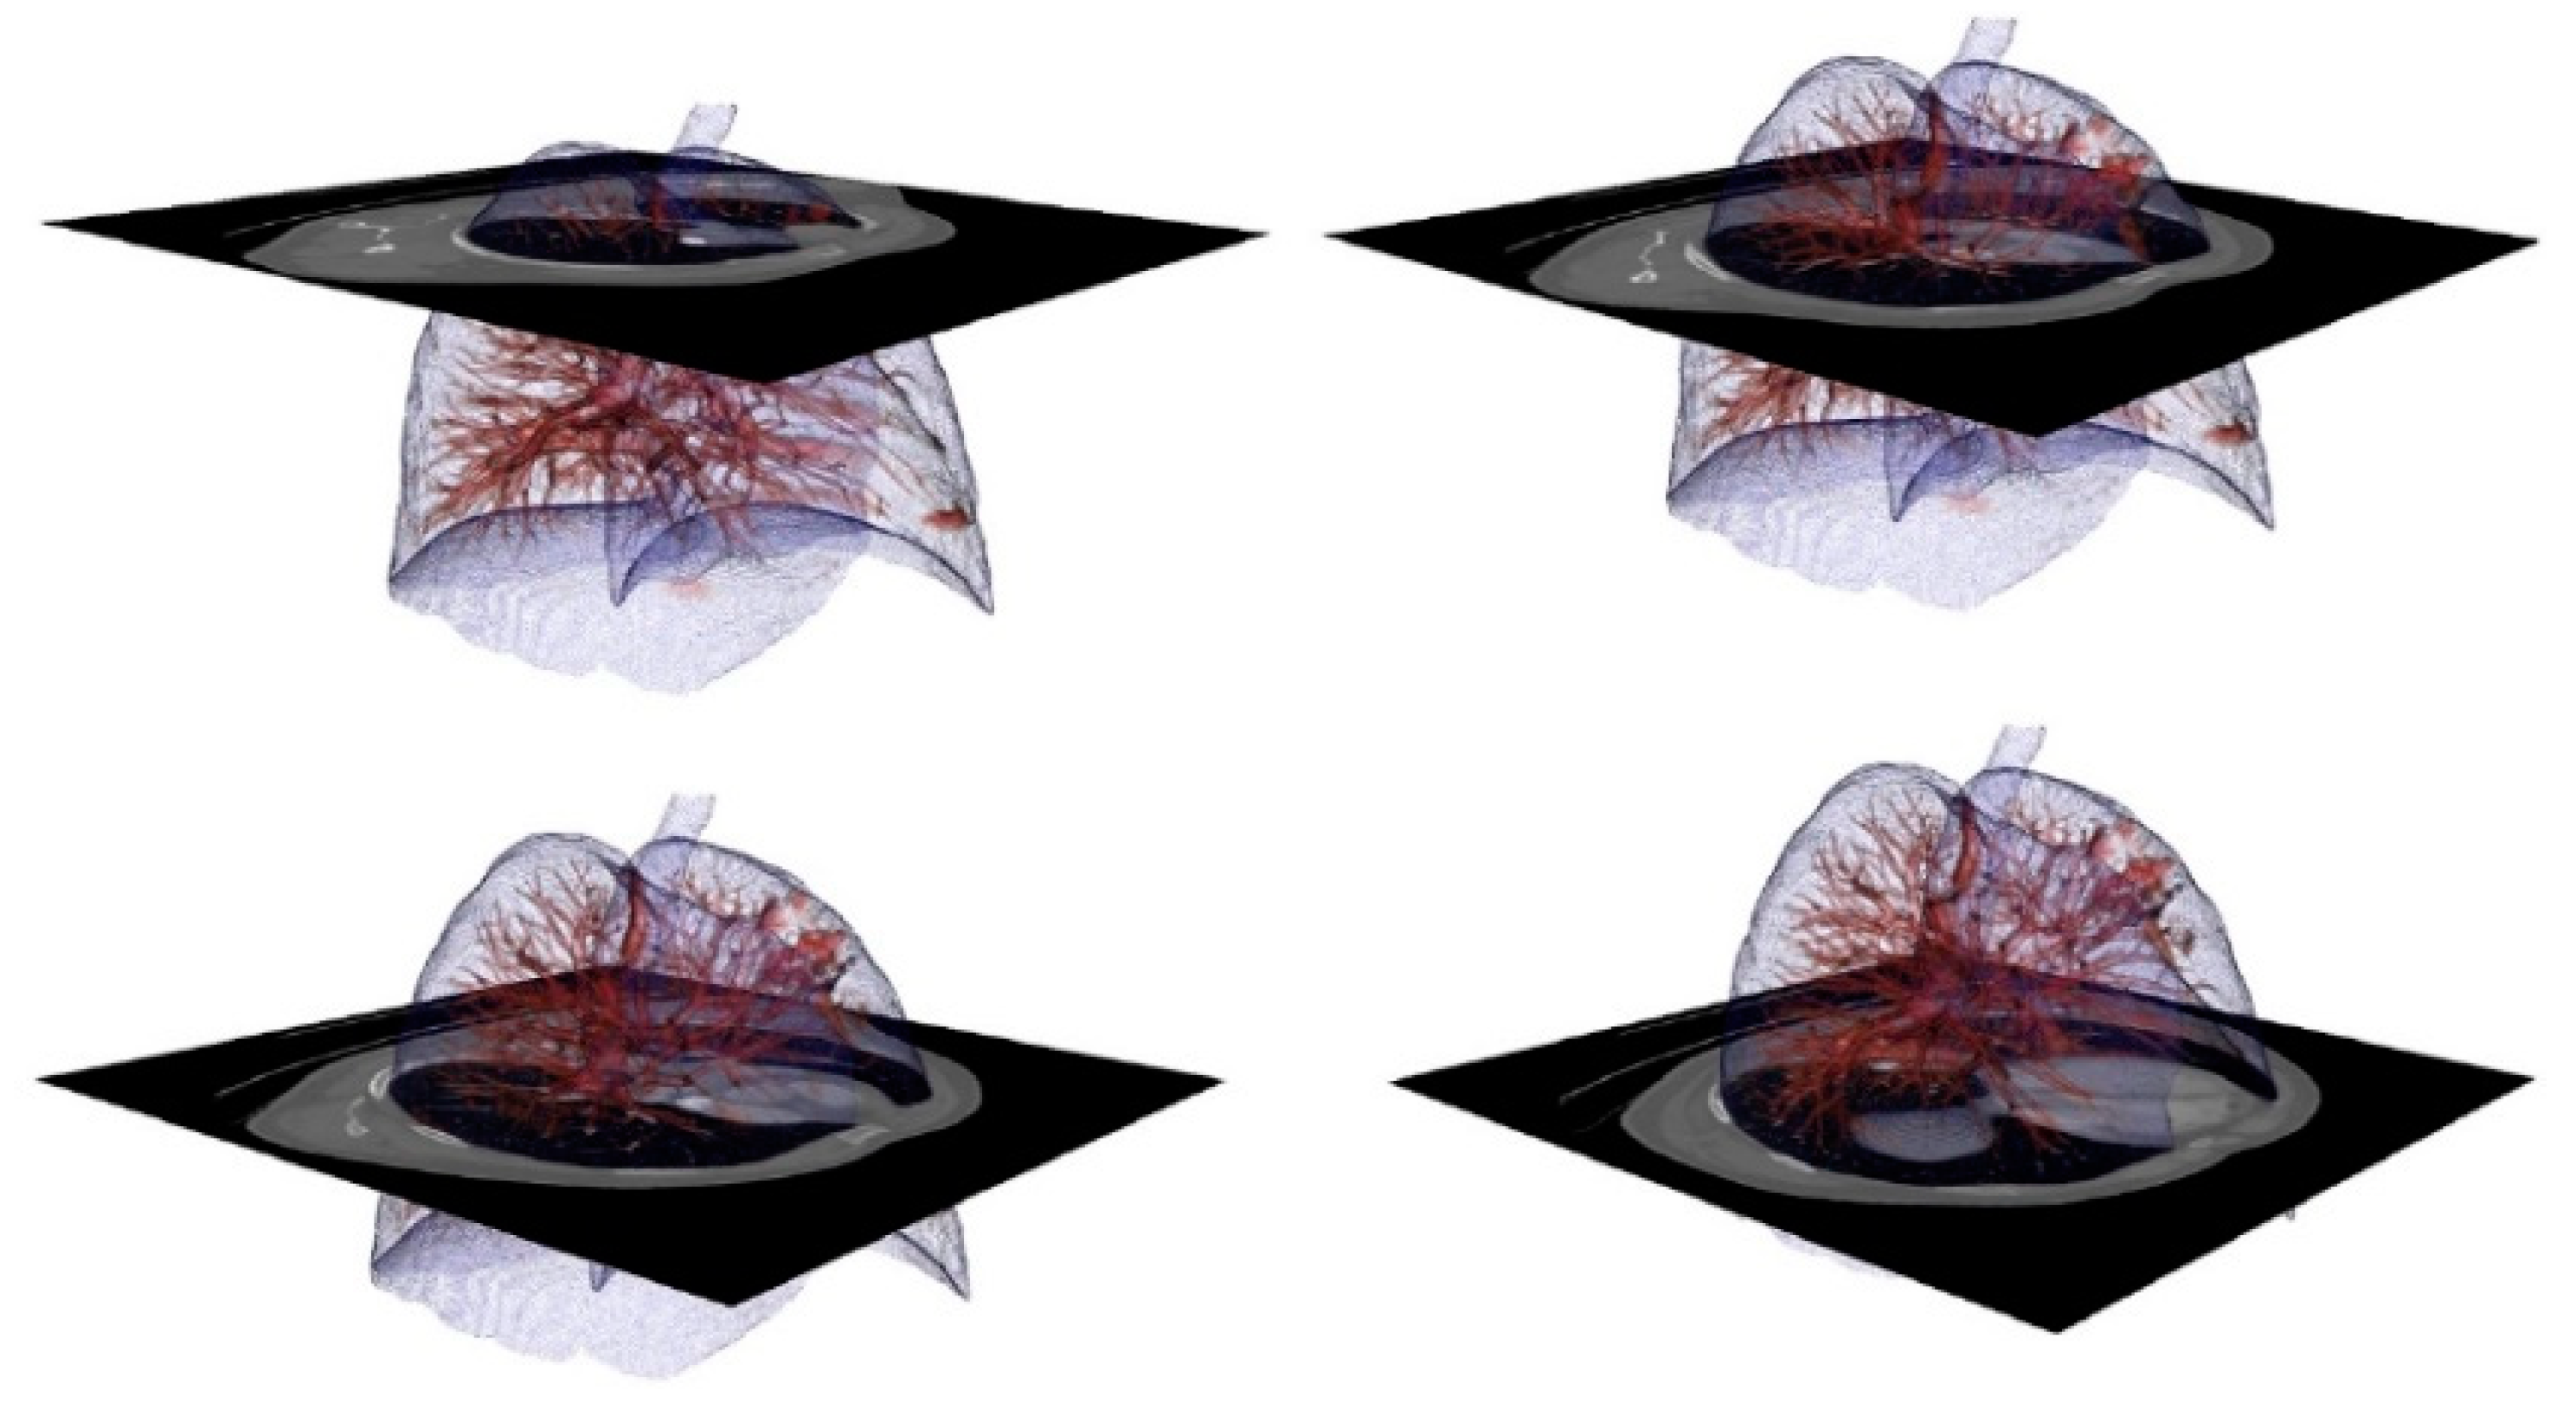

2.4. 3D Reconstruction and Storage

3.2. Results Visualization